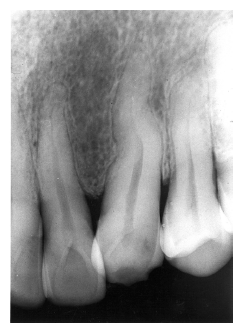

Invagination (Dens in Dente)

Invagination represents a deep infolding of the tooth with extension of the enamel down through the dentin into the pulp. Such teeth can be severely deformed, appearing with an enlarged pulp chamber that has been likened to a tooth within a tooth (dens in dente).

The most commonly affected tooth is the permanent maxillary lateral incisor (Figure 34 and Figure 35). Single dens in dente are most common, but double varieties also occur.

Figure 35 - Invagination

Figure 35